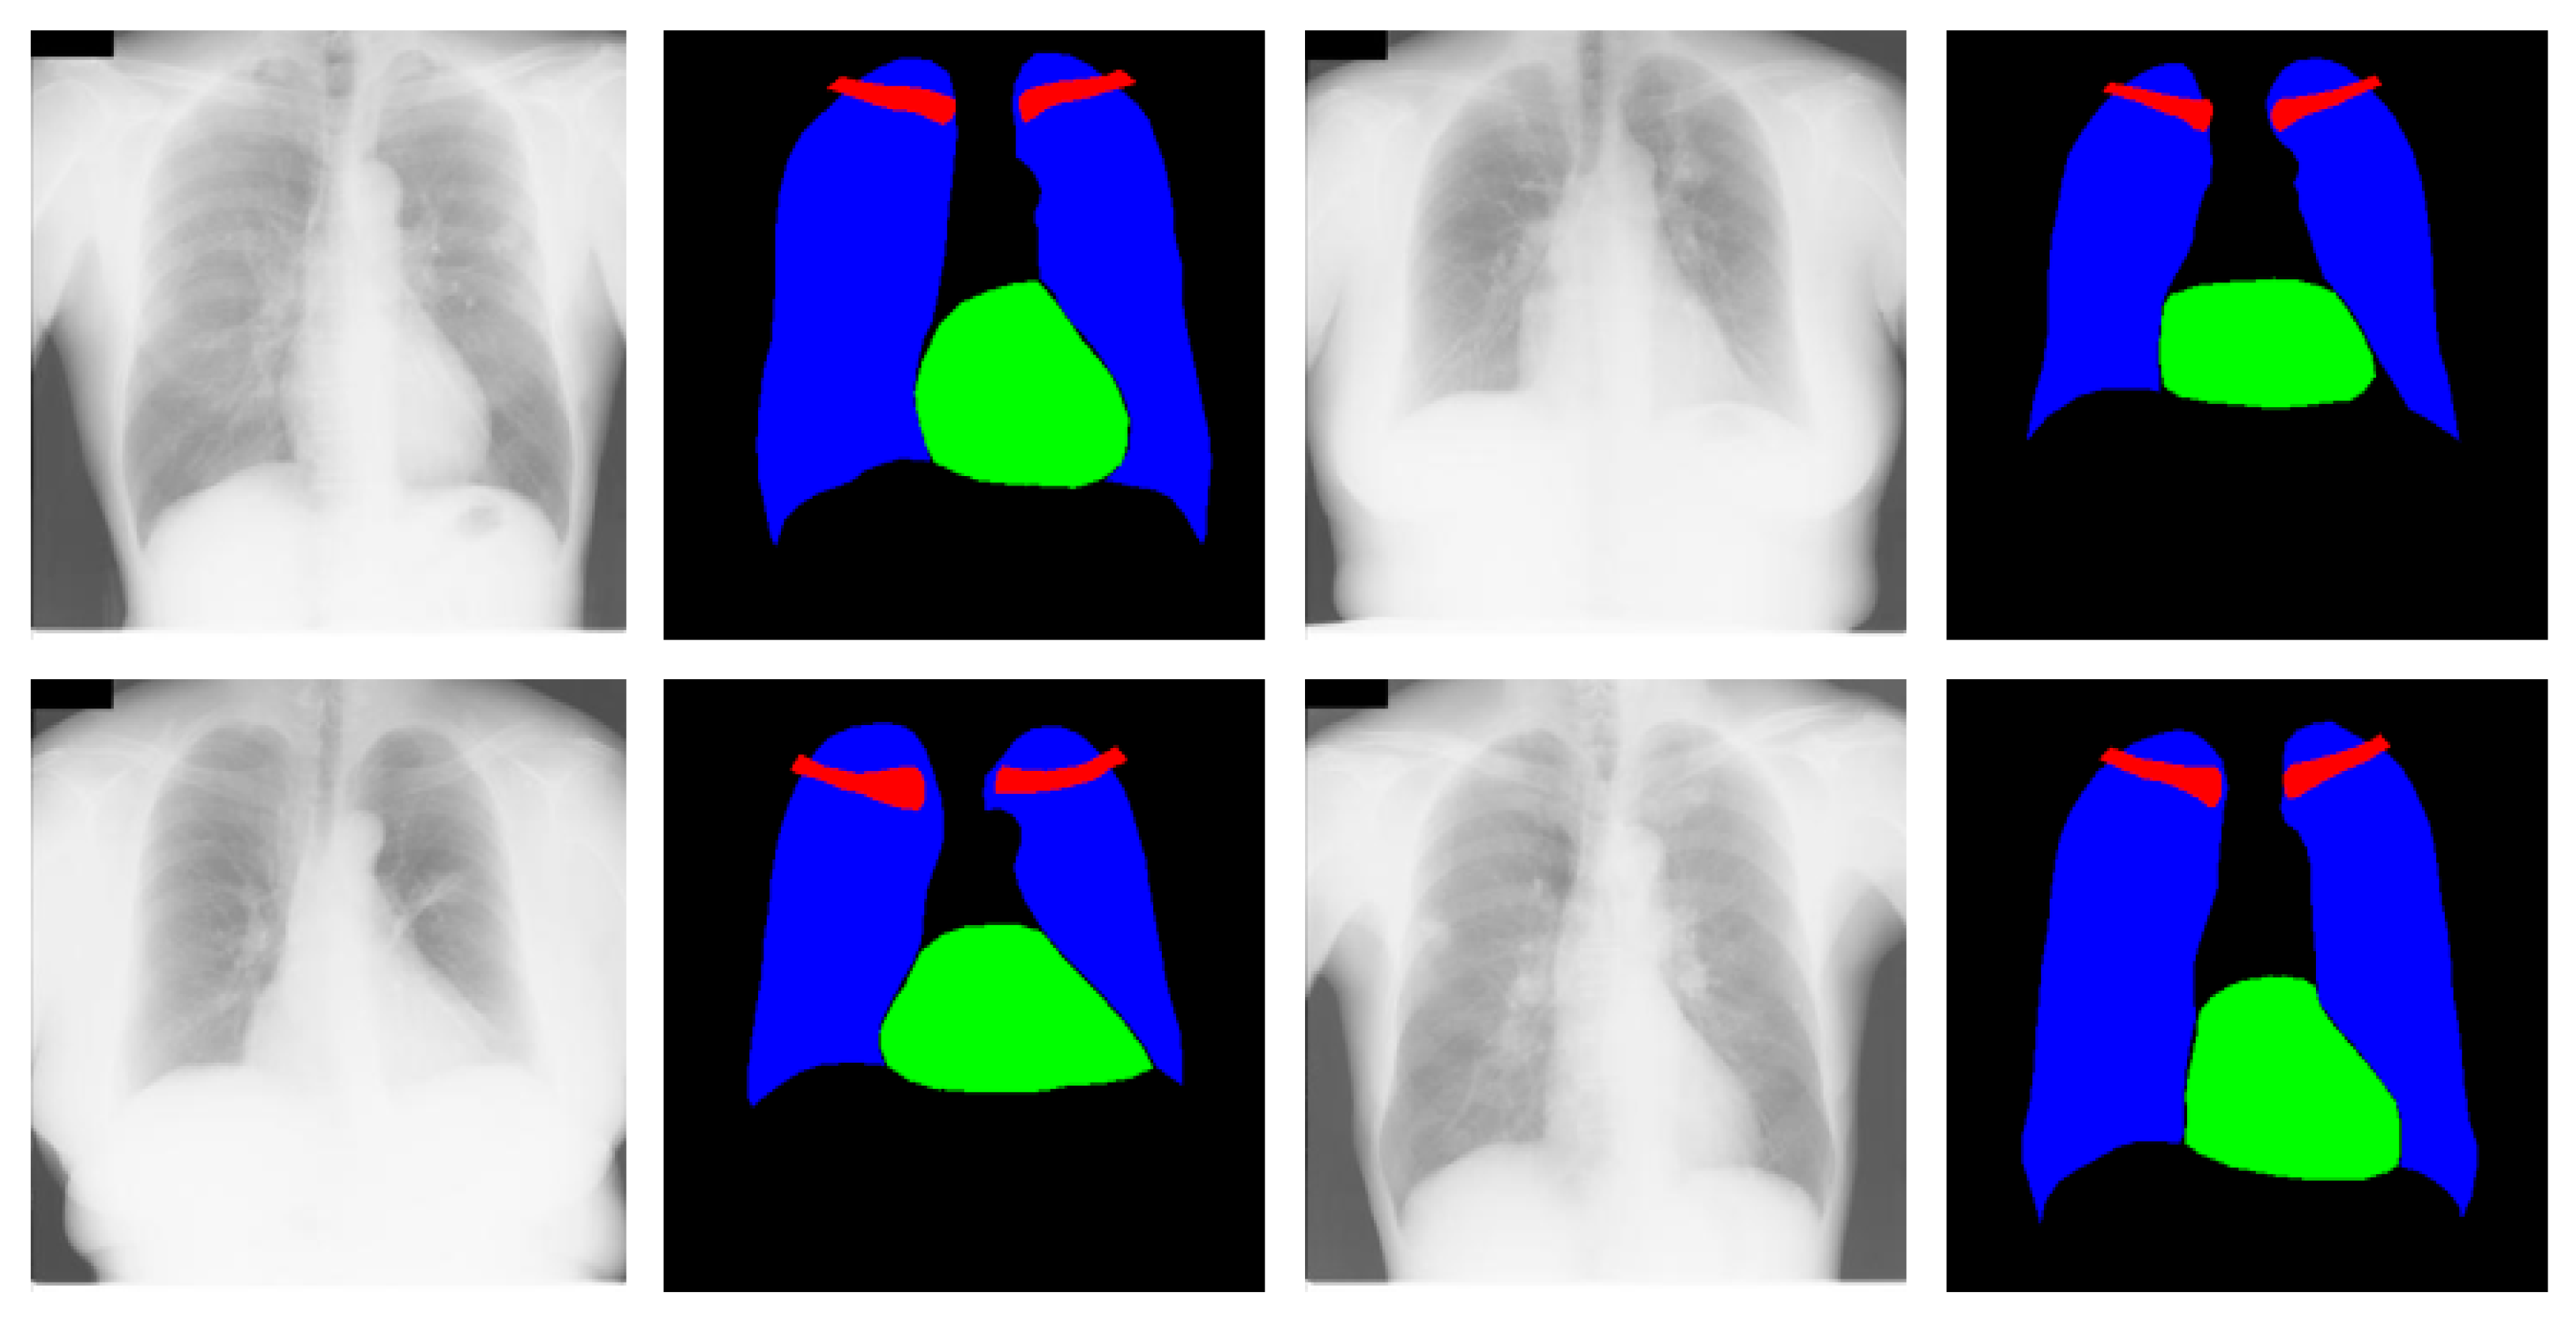

- X-RayNet does not require preprocessing for multiclass semantic segmentation to detect the lungs, heart, and clavicle bones at the same time. X-RayNet considers the importance of computational cost; therefore, X-RayNet-2 reduces the trainable parameters by 75% with a competitive performance.

3.4.2. Chest Organ Segmentation Results by X-RayNet